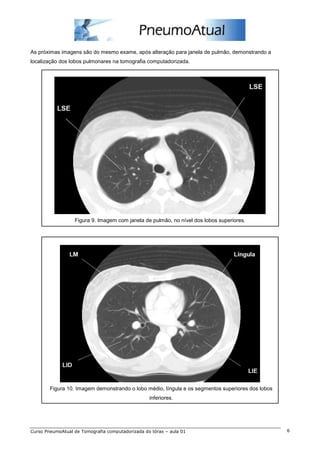

As próximas imagens são do mesmo exame, após alteração para janela de pulmão, demonstrando a

localização dos lobos pulmonares na tomografia computadorizada.

Figura 9. Imagem com janela de pulmão, no nível dos lobos superiores.

Figura 10. Imagem demonstrando o lobo médio, língula e os segmentos superiores dos lobos

inferiores.

As próximas imagenssão do mesmo exame, após alteração para janela de pulmão, demonstrando a localização dos lobos pulmonares na tomografia computadorizada. Figura 9. Imagem com janela de pulmão, no nível dos lobos superiores. Figura 10. Imagem demonstrando o lobo médio, língula e os segmentos superiores dos lobos inferiores. Curso PneumoAtual de Tomografia computadorizada do tórax – aula 01 6